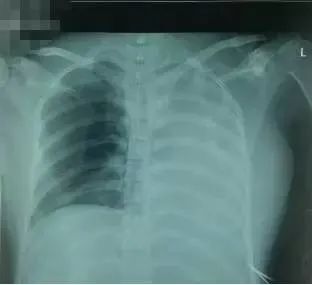

引流后于11月22日再拍胸片(图3)才诊断左肺不张,气管插管过深。立即将气管插管退至距门齿21cm。当气管插管退入主气管后,呼吸机参数和血气值都有明显改善(表1、表2)。

图3 ?在引流左侧胸腔积液后,左侧肺不张未改善,才发现气管插管进入右主支气管